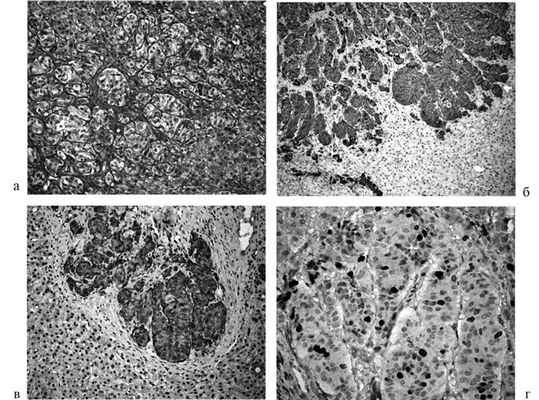

Биопсия печени выявила метастаз высокодифференцированной эндокринной карциномы, состоящей из островков и тяжей опухолевых клеток с развитой эозинофильной цитоплазмой, мономорфными мелкими ядрами с низкой митотической активностью, без очагов некроза. Почти все опухолевые клетки были позитивными в иммуногистохимических реакциях с антителами к соматостатину, хромогранину А, нейронспецифической энолазе и синаптофизину (рис. 3). Рисунок 3. Микроскопическое строение метастаза соматостатинпродуцирующей карциномы в печени. А — островки и тяжи опухолевых клеток, инфильтрирующих ткань печени. Окраска гематоксилином и эозином. В — С — все опухолевые клетки позитивны в иммуногистохимических реакциях с антителами к синаптофизину (В) и соматостатину (С). D — некоторые ядра опухолевых клеток позитивны к Ki-67. Ув. 250 (A—C), 400 (D). Небольшая часть опухолевых клеток была позитивна в реакции с антителами к кальцитонину. Отмечены негативные реакции с антителами к АКТГ, инсулину, глюкагону, гастрину и вазоактивному интестинальному пептиду.